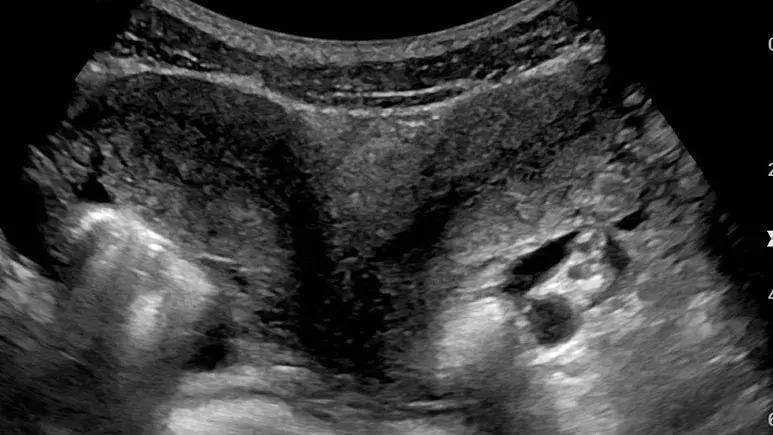

به گزارش سایت دیده بان ایران؛ پزشکان می‌گویند یک زن ۳۲ ساله اهل آلاباما در آمریکا که یک جفت رحم در بدن دارد، در هر دوی آنها باردار شده است. این پدیده به حدی نادر است که تقریبا تمامی متخصصان زنان و زایمان در طول حرفه طبابت خود با چنین موردی روبرو نمی‌شوند.«کلسی هچر» می‌گوید از ۱۷ سالگی می‌دانسته مبتلا به یک بیماری نادر به نام «رحم دیدلفیس» است که در آن فرد دارای رحمی دوگانه است. تصور می‌شود که تنها حدود ۰.۳ درصد از زنان با دو رحم به دنیا می‌آیند.خانم هچر از بارداری خود مطلع بود، اما نمی‌دانست که وضعیت جنین‌اش چگونه است. تا اینکه پزشکان در معاینات معمول ویژه هشت هفتگی بارداری متوجه شدند او نه تنها دو فرزند به دنیا می‌آورد، بلکه دریافتند هر کدام از این دوقلوها نیز در یکی از رحم‌ها قرار دارند.

خانم هچر از بارداری خود مطلع بود، اما نمی‌دانست که وضعیت جنین‌اش چگونه است. تا اینکه پزشکان در معاینات معمول ویژه هشت هفتگی بارداری متوجه شدند او نه تنها دو فرزند به دنیا می‌آورد، بلکه دریافتند هر کدام از این دوقلوها نیز در یکی از رحم‌ها قرار دارند.